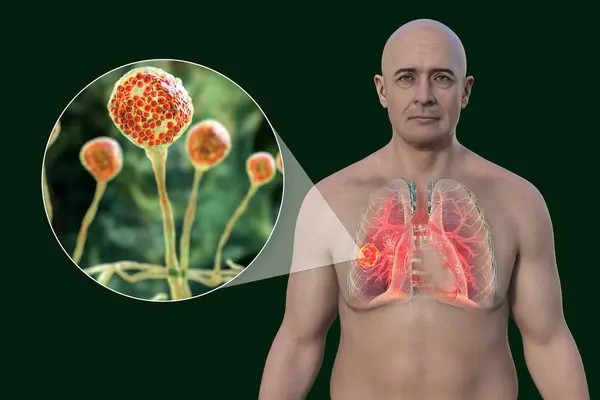

- يصيب النوع الرئوي الرئتين ويظهر غالبا لدى مرضى ضعف المناعة الشديد أو من يخضعون للعلاج الكيميائي.

- يؤثر النوع الجلدي في الجلد نتيجة دخول الفطريات عبر الجروح أو الحروق.

يعتمد تشخيص مرض الفطر الأسود على مجموعة من الفحوص الطبية الدقيقة التي تهدف إلى تأكيد وجود العدوى وتحديد موقعها ومدى انتشارها داخل الجسم، وتشمل:

- التصوير المقطعي المحوسب.